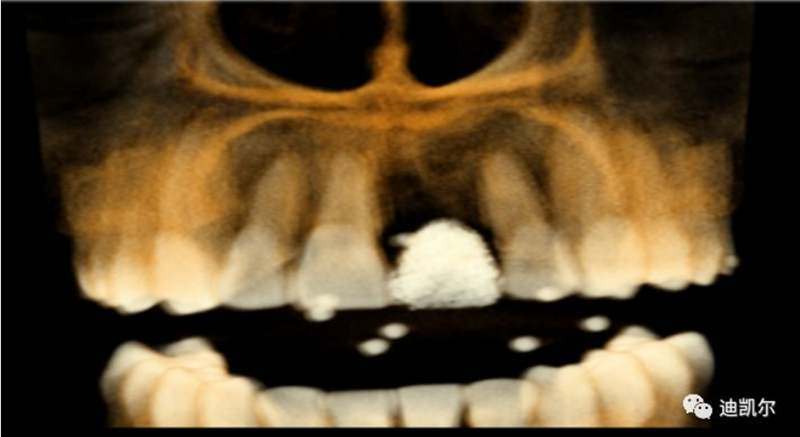

術(shù)前CBCT圖像和測量數(shù)據(jù)

*前牙美學區(qū)種植,病人為正畸治療后,對美學要求高

*早期種植病例,頰側(cè)組織凹陷,肉眼可見骨缺損,需要種植同期GBR

*CBCT顯示骨缺損嚴重,種植窩洞制備困難,種植體很難獲得初期穩(wěn)定性

*修復(fù)體設(shè)計為舌側(cè)窩穿出螺絲固位,對種植體位置和長軸要求很高